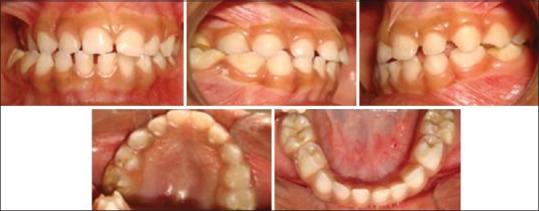

Unilateral condylar hyperplasia is an uncommon condition with unknown etiology which causes overdevelopment of condyle leading to facial asymmetry, mandibular deviation, malocclusion, and articulation dysfunction. Two Indian families with unilateral condylar hyperplasia are presented where the similar abnormality was also detected in one of their parents. The condylar hyperplasia in these two families indicates that mandibular condylar hyperplasia could be genetic in origin.

单侧髁突增生是一种病因不明的罕见病症,它会导致髁突过度发育,进而引起面部不对称、下颌偏斜、错牙合畸形及关节功能障碍。本文报告了两个患有单侧髁突增生的印度家族,在他们的一位家长中也检测到了类似异常。这两个家族中的髁突增生表明下颌髁突增生可能起源于遗传。